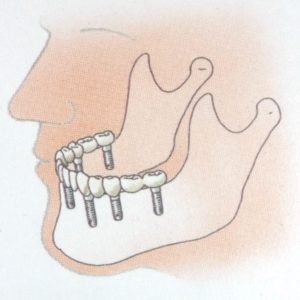

- Bij het ontbreken van één tand of kies, wordt een implantaat ter plaatse van het ontbrekende gebitselement in de kaak geplaatst en wordt daarop een kroon van keramiek of een combinatie van keramiek met metaal vastgezet..

- Bij het ontbreken van enkele tanden of kiezen plaatst men twee of meer implantaten en maakt men een vastzittende brug. Deze brug vervangt de ontbrekende tanden en/of kiezen.

- Bij het ontbreken van alle tanden en kiezen.

- worden twee of meer implantaten geplaatst. Daarop worden knopjes of staafjes gemaakt waarop een overkappingsprothese vastklikt. Deze is uitneembaar, maar zit wel veel vaster dan een normale gebitsprothese. Soms wordt er een niet-uitneembare brug op vervaardigd, maar dan heb je wel tenminste vier implantaten nodig en is de behandeling veel duurder omdat de verzekeraar een dergelijke behandeling in het algemeen niet vergoedt.